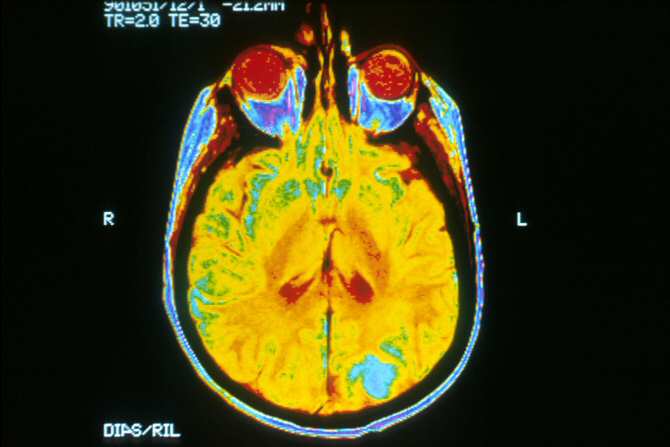

Imagen de un cerebro humano captada mediante resonancia magnética. (Foto: Dr. Leon Kaufman, University Of California, San Francisco)